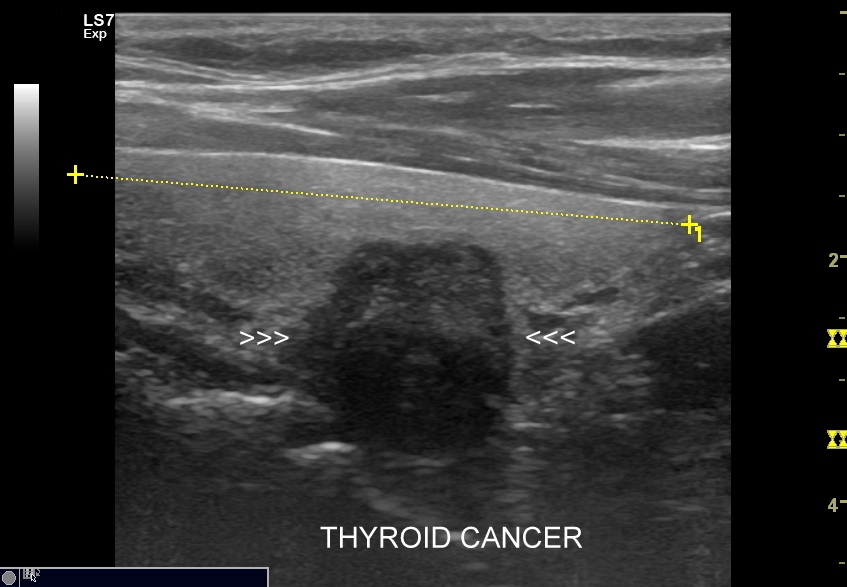

10. Guzy tarczycy. Klasyfikacja TIRADS.

Multiparametryczne badanie USG (MPUS) jest rozwinięciem klasycznego USG tarczycy i szyi pod postacią jednoczasowego zastosowania różnorodnych technologicznie trybów obrazowania USG, zarówno tzw. „nowych”, jak i „starych”. Wśród nowych najważniejszym jest obrazowanie mikrounaczynienia (MVI / MVF), w dalszej kolejności tryb elastograficzny oraz B-flow. Wymienione „nowe” modalności w połączeniu ze „starymi”, przede wszystkim z Dopplerem spektralnym i color-Dopplerem, stanowią rdzeń nowoczesnej ultrasonografii MPUS, gdyż umożliwiają pozyskanie znacznie większej ilości informacji z badania USG szyi w porównywalnym przedziale czasowym, a przez to uzyskanie jego większej wartości diagnostycznej.

Przykładowo badanie MPUS umożliwia różnicowanie guzów, ocenę żywotności tkanek i biologii nowotworów, poprawia obrazowanie dużych naczyń krwionośnych oraz ocenę podejrzanych torbieli. Z kolei zastosowanie badania USG z kontrastem (CEUS), jako kolejnej modalności rozszerzającej MPUS, daje w wyselekcjonowanych przypadkach korzyści m. in. w postaci różnicowania i oceny zmian ogniskowych, czy oceny skuteczności terapii ablacyjnych.